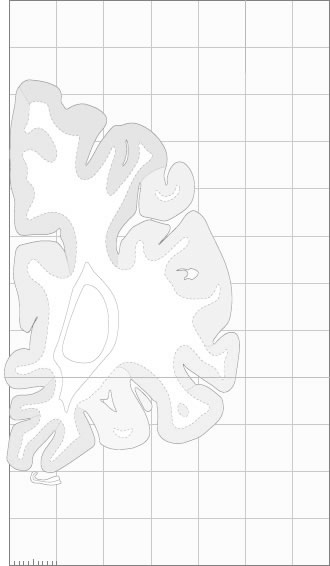

Schematic